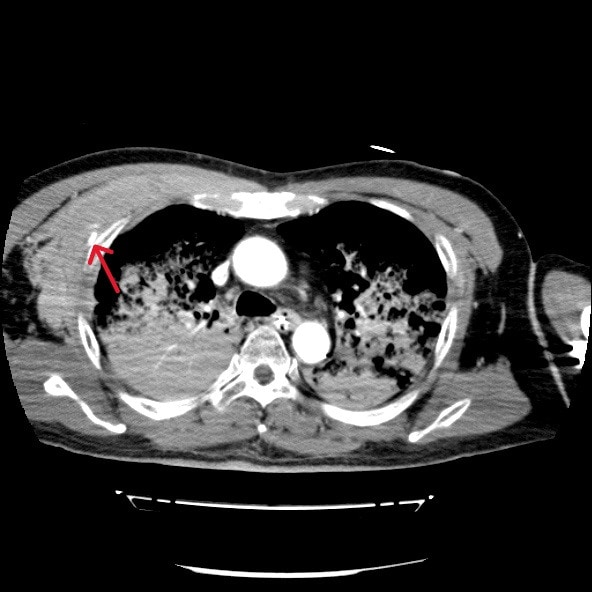

心筋梗塞によって心室細動をきたし心肺停止状態で当院に救急搬送された症例。救命活動が行われ心肺蘇生することができた。その後の経皮的冠動脈インターベンション(Percutaneous Coronary Intervention:PCI)の施行中に経皮的心肺補助法(Percutaneous Cardiopulmonary Support:PCPS)からの脱血不良あり循環血漿量減少が著明に進行していたため、原因精査目的に造影CTを撮影したところ、右第3肋骨周囲の前胸部に血管外漏出(extravasation)が認められた。

胸骨圧迫による動脈損傷が考えられたため、当院放射線科医師により緊急アンギオが施行された。右最上胸動脈および胸肩峰動脈からの出血が確認され、動脈塞栓術(TAE)にて止血することができた。

胸骨圧迫は心肺蘇生において不可欠な救命処置であるが、強い外力により外傷性合併症のリスクが存在する。代表的な合併症としては肋骨骨折や胸骨骨折の頻度が最も高く報告されており、血胸や胸壁血腫などの出血性合併症は報告により約10%程度とされている。ただし、出血源については明確ではなく、動脈損傷に関する症例報告は非常に稀である。特に内胸動脈や肋間動脈、最上胸動脈などの小血管損傷は画像検査が実施されなければ見逃される可能性が高く、臨床的にも認識されにくい。

本症例は、胸骨圧迫後に右最上胸動脈および胸肩峰動脈からの出血を認めた合併症例である。これまでの文献においても、胸骨圧迫後にこれらの動脈からの出血が明確に確認された症例はほとんど存在せず、本症例はその点で非常に特異性が高い。

本症例においては造影CTが循環不全の原因特定、胸骨圧迫による血管損傷の可視化、出血量評価、他臓器損傷のスクリーニングおよび治療方針の決定に有用であった。本症例のような稀な合併症を見逃さないためにも、胸骨圧迫後の症例では、一般的な骨折だけでなく、稀な血管損傷の可能性も念頭に置き、早期に造影CTによる精査を積極的に行うことが重要である。